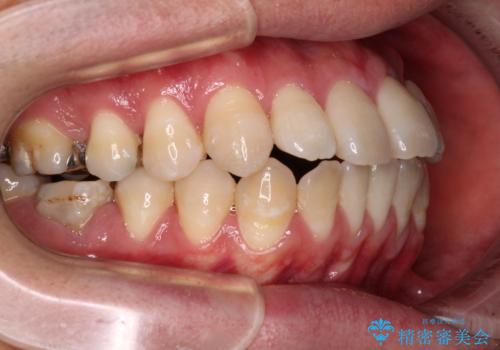

精密検査の結果、上下左右の小臼歯4本を抜歯し、そのスペースに前歯を後方へ移動させる矯正治療をご提案しました。

少しずつ前歯を後ろに下げていくことで、横顔のラインが整い、口元の“出っ張り感”が解消。